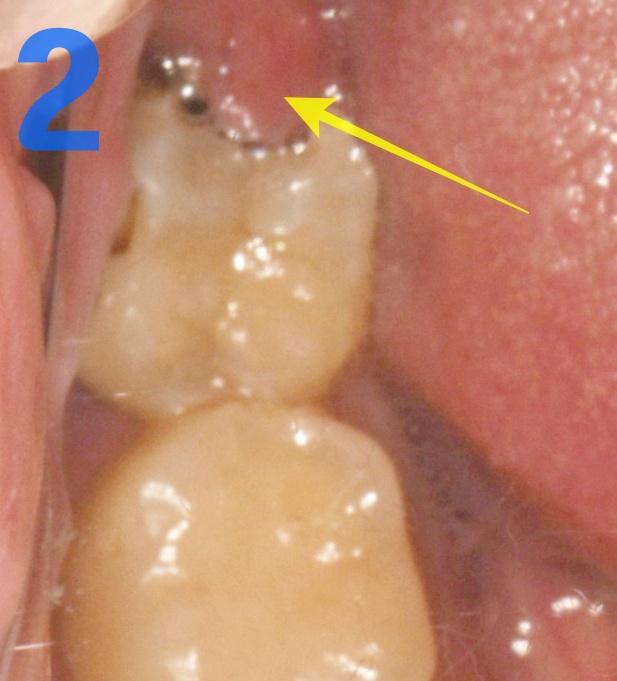

사진 1번 보세요. 저기 노란색 화살표 부위 잘 닦으실 수 있나요? 매우 어렵습니다.

사진 2번 보시면 노란색 화살표가 가리키고 있는 부위는 사랑니를 덮고 있는 잇몸입니다.

잇몸이 씹혀서 빨갛게 부은 것 보이죠? 당연히 아프겠죠. 이런 경우는 치관 주위염과 씹히는 통증이 함께 있어서 더욱 아플 거예요.

사진 1,2번과 같은 상태가 오랫동안 유지되면 사랑니(노란 화살표) 뿐 아니라 그 앞의 치아까지도(초록 화살표) 충치가 생깁니다.